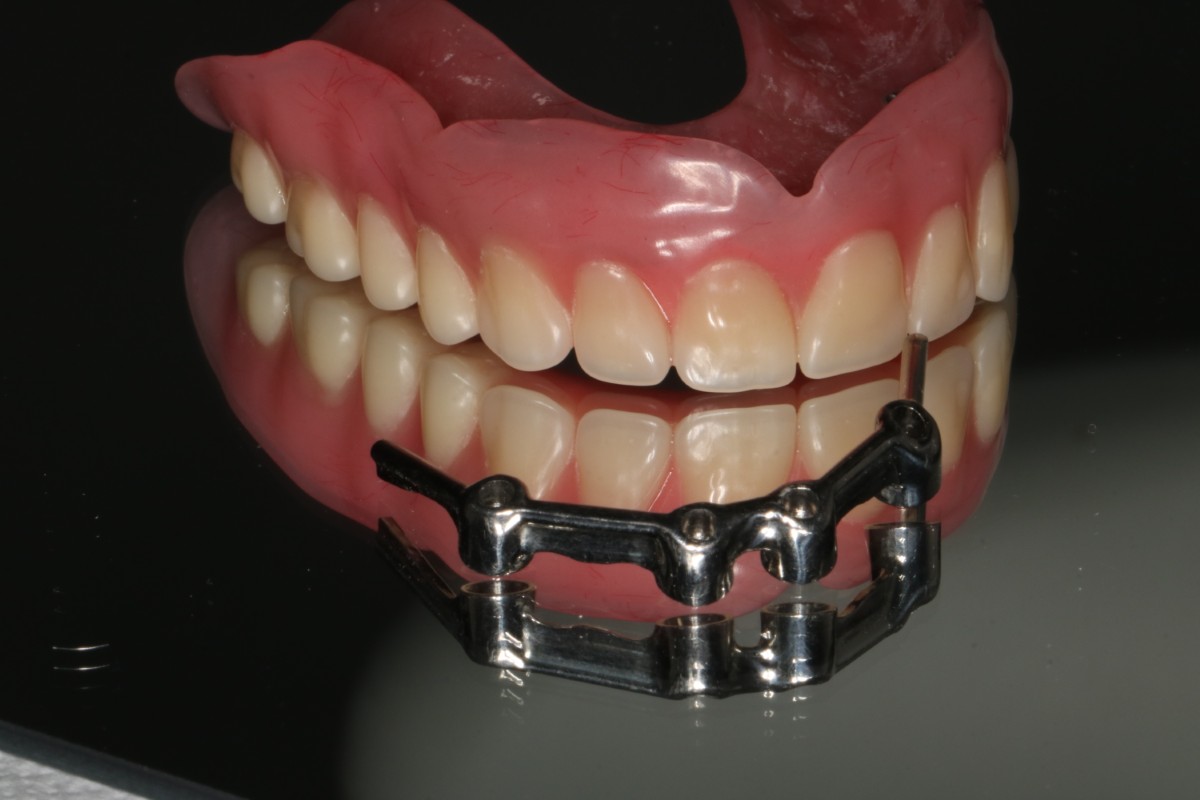

3. Protezy na koronach teleskopowych – elegancja i precyzja

Korony teleskopowe to najbardziej zaawansowane technicznie rozwiązanie w protetyce ruchomej na implantach. System działa na zasadzie “korona w koronie” – na implanty osadzone są stałe korony (korony pierwotne), a na nie nakładana jest proteza z koronami wtórnymi, które idealnie do nich przylegają.

Zasada działania:

Na każdy implant zakręcana jest precyzyjnie wykonana korona pierwotna. Proteza posiada wewnątrz odpowiadające im korony wtórne. Połączenie typu teleskopowego zapewnia doskonałe dopasowanie i retencję mechaniczną – proteza “wsuwana” jest pionowym ruchem i trzyma się niezwykle stabilnie bez dodatkowych zapięć.

Przypadek 2